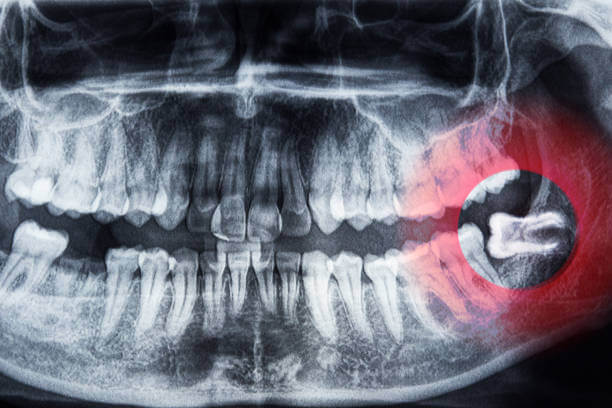

사랑니는 보통 17세~25세 사이에 나오는 제3대구치입니다. 하지만 정상적으로 나오지 못하고 잇몸이나 턱뼈 속에 묻힌 경우를 매복 사랑니라고 합니다.

제가 근무했던 치과에 내원한 한 장병은 입대 전에는 증상이 없어 매복 사랑니 발치를 미뤘습니다. 그러나 훈련 중 갑작스럽게 볼이 붓고 턱이 잘 벌어지지 않는 증상으로 응급 내원했습니다.

그는 이미 고열과 염증이 진행돼 군 치과에서 치료 불가 판정을 받아 급히 외부 치과로 전원됐고, 훈련에서 2주 이상 빠져 큰 스트레스를 겪었습니다.